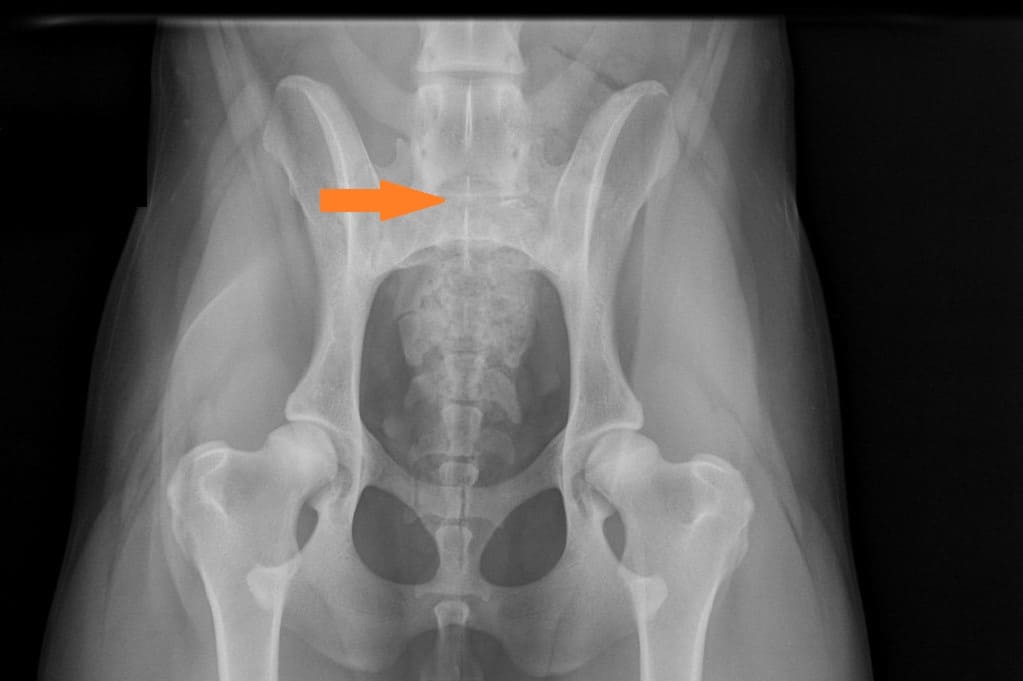

LTV2; symmetrinen

LTV3; epäsymmetrinen; oikeanpuoleisessa VD-kuvassa S1 on vasemmalla puolella ristinikaman ja oikella puolella lannenikaman kaltainen okahaarakkeen kera.

LTV3, epäsymmetrinen lanne-ristinikama näyttää olevan muita muotoja harmillisempi. Joissain tapauksissa epäsymmetriseen lanne-ristinikamaan liittyy vino lantio, joka saattaa aiheuttaa myös lonkkien epätasaista kehitystä. Tämä on varsin loogista; kun lantio on vino kohdistuu paine lonkkamaljoille epätasaisesti. Pidemmän ajan kuluessa epätasapaino voi kuluttaa toista lonkkamaljaa nopeammin ja aiheuttaa tätä kautta nivelrikkoa.

KoiraNetin mukaan 38,9% LTV3-lausunnon saaneista rhodesiankoirista on saanut lonkkien osalta lausunnon, jossa toinen lonkka on 1-2 astetta toista huonompi, esimerkiksi A/C (lokakuu 2020). Tutkimustulos LTV3 ei kerro koiran lantion asentoa.

”Asymmetrical LTV favours pelvic rotation over its long axis, resulting in inadequate femoral head coverage by the acetabulum on one side. Inadequate coverage of the femoral head favours subluxation, malformation of the hip joint, and secondary osteoarthritis. Asymmetrical hip conformation may therefore be the sequela of a LTV and mask or aggravate genetically induced canine hip dysplasia.”

(Flückiger M., Frank Steffen F. et al 2017)